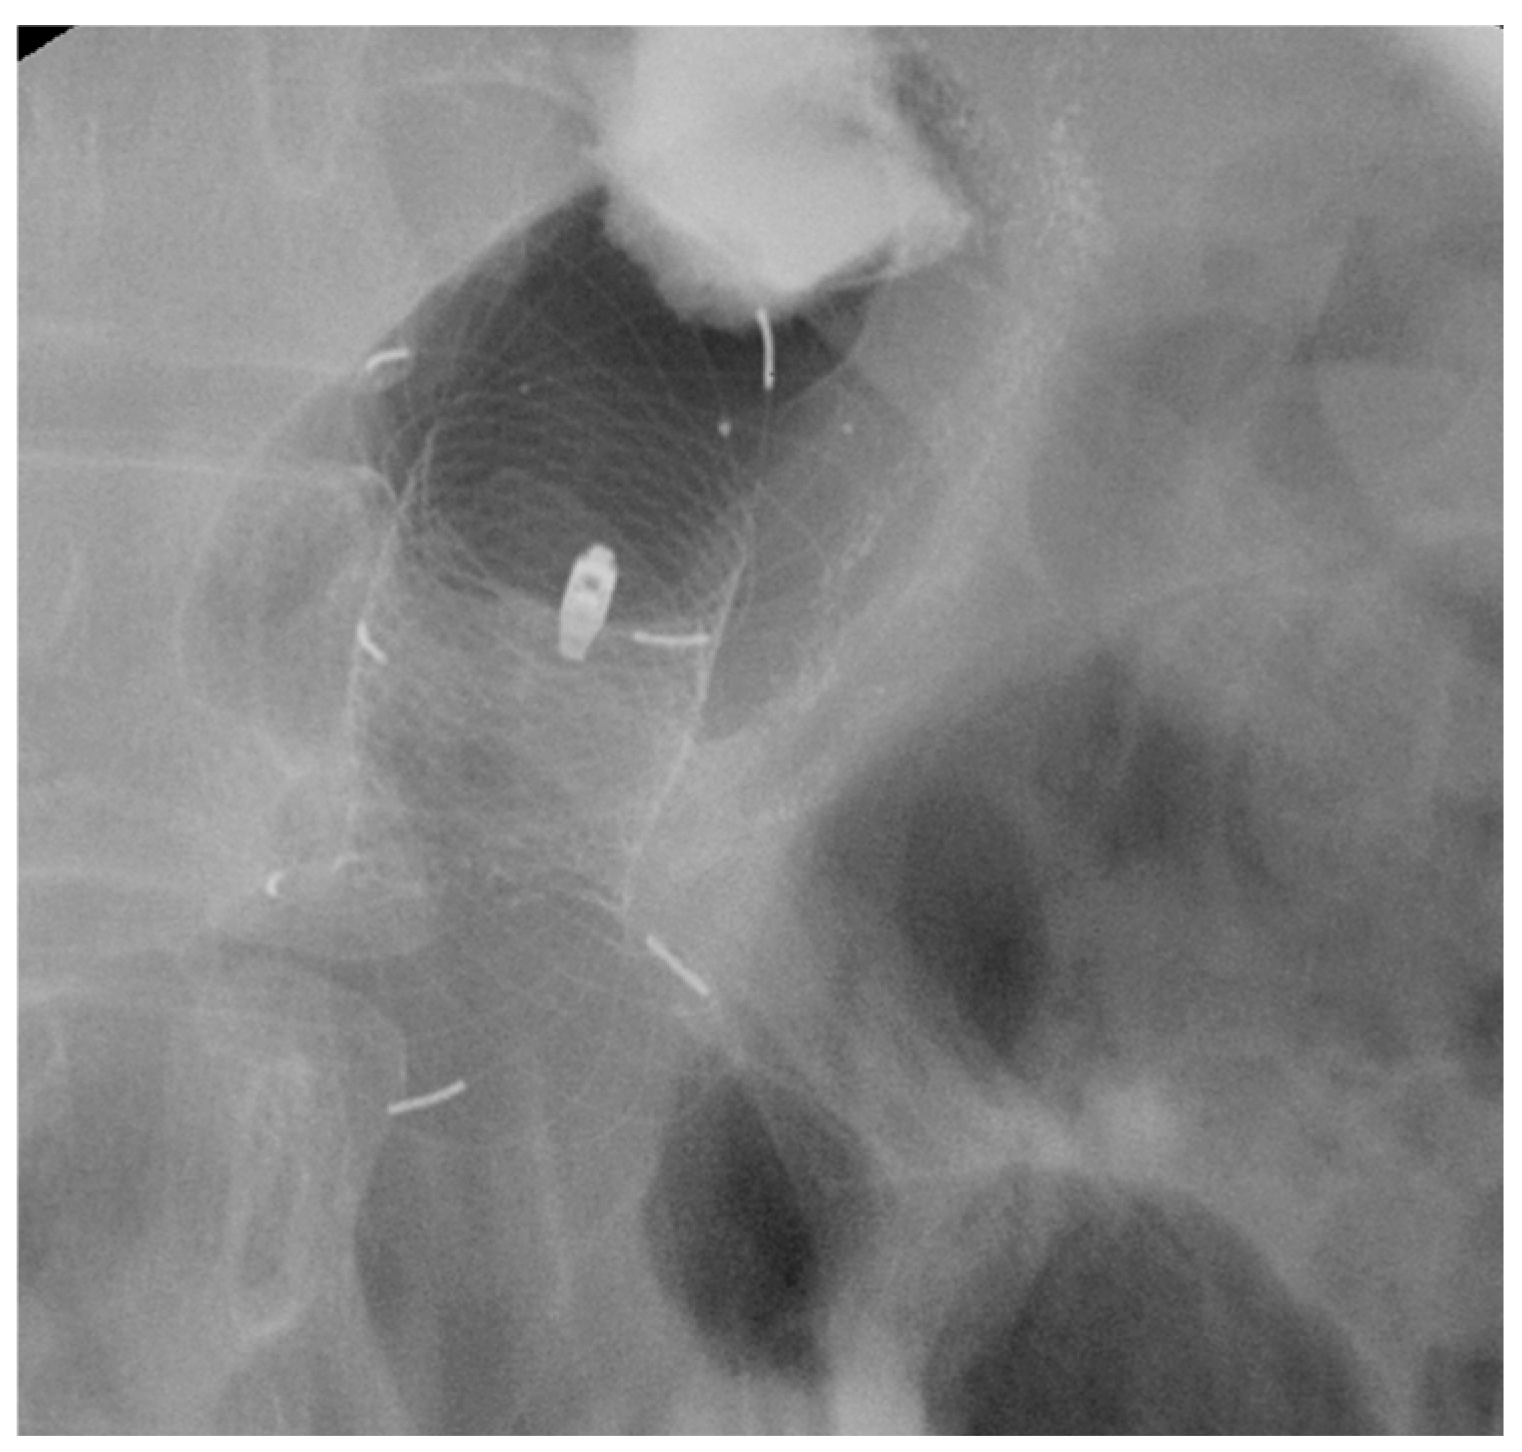

3.1.3. VAC Stent

SEMS vs. VAC Stent